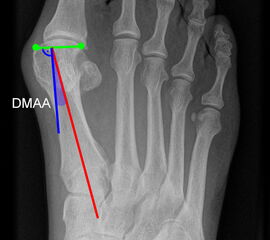

Beurteilung von Fehlstellungen des Vorfußes

Zur Vollansicht und zum Lesen der Bildbeschreibung bitte die Bilder anklicken.

Gelenkflächenwinkel

DMAA (Distal metatarsal artikular angle, Syn. Gelenkflächenwinkel): Winkel zwischen der Achse des Os metatarsale I (rot) und dem Lot auf die distale Gelenkflächenebene (blau) des Os metatarsale I. Die Gelenkflächenebene (grün) wird definiert durch zwei Punkte, welche die mediale und laterale Begrenzung der Gelenkfläche definieren (Norm: <10° 5). Die Projektion des DMAA ist stark abhängig von der Rotation des Os metatarsale I 7. Daher ist bei der operativen Behandlung des Hallux valgus eine Beurteilung häufig erst nach Korrektur der Pronationsstellung des Os metatarsale I möglich. Tendenziell wird der DMAA auf präoperativen Röntgenaufnahmen überschätzt.